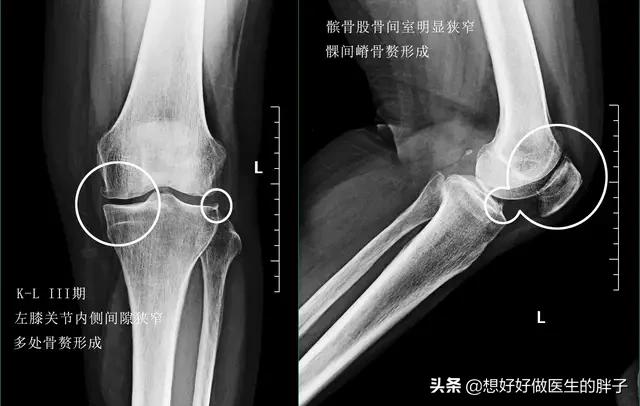

所以从理论上来讲,骨赘是属于帮助我们身体维持稳定性的一种结构,但是当关节软骨进一步的磨损,骨赘会越来越大,就会刺激到周边的软组织、韧带、神经等组织与结构,导致患者出现明显的疼痛,当检查x线的时候会发现这些骨赘形成类似刺状,于是骨刺这个说法就诞生了……!

当关节软骨磨损处于中期的时候,患者不仅会在上下楼梯的时候出现疼痛,在走平路的时候也会有明显的关节不适感,而且有的患者在出生的过程中会有明显的响声,有部分患者在这个阶段会出现关节腔内的积液,但是量不会特别大。此时的治疗在坚持康复锻炼为基础的前提下,应该给予关节腔内进行玻璃酸钠注射治疗,帮助增加关节内的软骨弹性,减少关节内软骨的磨损,帮助控制关节的症状;因为此时患者的关节内磨损比较重,在口服氨糖可能并不能帮助患者缓解症状。

到了关节软骨磨损的晚期,很可能关节内负重区的软骨已经被磨得消失殆尽了。所以患者的关节往往会出现明显的间隙狭窄和大量的骨赘形成,此时的患者,严重的关节屈伸角度也会有明显的受限,而且疼痛会对患者的整个生活造成非常大的困扰,有些比较重的患者甚至会出现休息的时候关节也疼痛,而且在夜间休息的时候能疼醒,此时以前的一些治疗方法就很难帮助患者解决问题了,进行关节置换或者是部分关节置换,是解决患者问题的最佳措施(康复锻炼一样要做)。